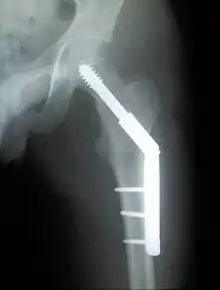

For low-grade fractures (Garden types 1 and 2), standard treatment is fixation of the fracture in situ with screws or a sliding screw/plate device. This treatment can also be offered for displaced fractures after the fracture has been reduced.

The latest evidence suggests that there may be little or no difference between screws and fixed angle plates as internal fixation implants for intracapsular hip fractures in older adults.[41] The findings are based on low quality evidence that can't firmly conclude major difference in hip function, quality of life, and additional surgery.

Closed reduction may not be satisfactory and open reduction then becomes necessary.[42] The use of open reduction has been reported as 8-13% among pertrochanteric fractures, and 52% among intertrochanteric fractures.[43] Both intertrochanteric and pertrochanteric fractures may be treated by a dynamic hip screw and plate, or an intramedullary rod.[42]

The fracture typically takes 3–6 months to heal. As it is only common in elderly, removal of the dynamic hip screw is usually not recommended to avoid unnecessary risk of second operation and the increased risk of re-fracture after implant removal. The most common cause for hip fractures in the elderly is osteoporosis; if this is the case, treatment of the osteoporosis can well reduce the risk of further fracture. Only young patients tend to consider having it removed; the implant may function as a stress riser, increasing the risk of a break if another accident occurs.